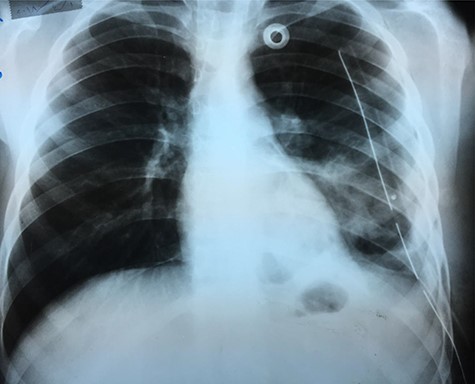

Chest X-ray (Fig. 1) showed an increased density in the left lower zone of the lung. Forty-eight hours later, the patient arrived at the ER along with the computed tomography (CT) scan (Fig. 2). He was in a very poor general condition with pallor, severe dyspnea and clouding of consciousness. Physical examination showed the absence of the left lung sounds, shifted apex beat of the heart to the right and a thready pulse and a blood pressure of about 80/40 mmHg.

An X-ray image (Fig. 4) was done 24 h after the operation, and it showed good improvement.